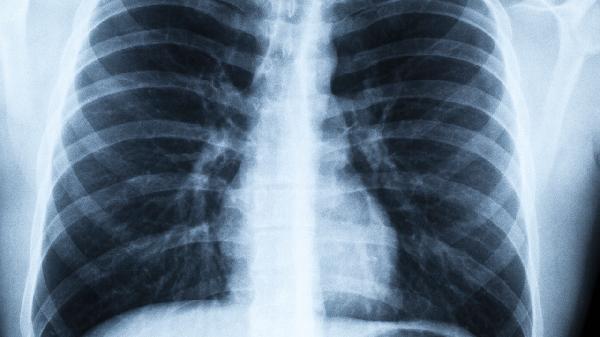

预防尘肺病需采取综合措施。用人单位应改进生产工艺,采用湿式作业方式抑制粉尘飞扬。劳动者必须规范佩戴防尘口罩,选择符合国家标准的N95级别防护用品。脱离粉尘环境后要及时清洗面部和鼻腔。定期进行胸部X线或肺功能检查有助于早期发现病变。对于已确诊患者,应调离粉尘岗位并接受规范治疗,避免病情进一步恶化。